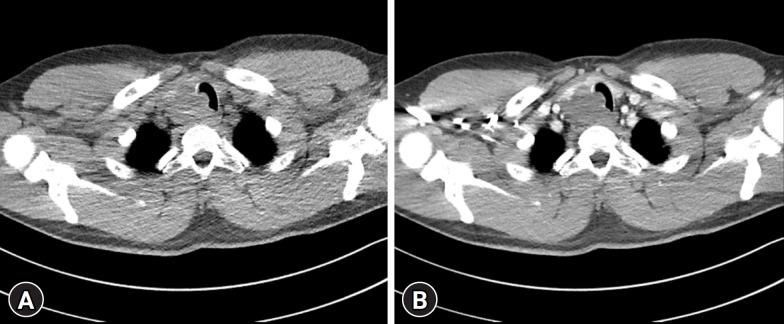

Plexiform schwannomas representing a rare subset, comprise 5% of all schwannomas. However, their occurrence in the thyroid gland is exceptionally rare. A 32-year-old male presented with an incidentally discovered, asymptomatic thyroid mass. Imaging revealed an approximately 5 cm heterogeneous solid mass on the right thyroid lobe extending to the upper mediastinum and directly invading the upper trachea. Under the suspicion of thyroid malignancy, the patient underwent right thyroidectomy. Histological examination confirmed a plexiform schwannoma with S100-positive spindle cells. Currently, the patient is undergoing outpatient follow-up, with no reported complications. To our knowledge, this is the first documented case of plexiform schwannoma of the thyroid gland within the English literature. This case highlights the diverse and unpredictable clinical manifestations of thyroid masses, emphasizing the importance of a multidisciplinary approach for diagnosing and managing rare entities, such as thyroid gland schwannomas.

丛状神经鞘瘤是一种罕见的亚型,占所有神经鞘瘤的5%。然而,它们在甲状腺中的发生极为罕见。一名32岁男性因偶然发现的无症状甲状腺肿块就诊。影像学检查显示右侧甲状腺叶有一个约5 cm的不均匀实性肿块,延伸至上纵隔并直接侵犯上段气管。因怀疑为甲状腺恶性肿瘤,患者接受了右侧甲状腺切除术。组织学检查证实为丛状神经鞘瘤,S100阳性梭形细胞。目前,患者正在门诊随访,未报告并发症。据我们所知,这是英文文献中首例有记录的甲状腺丛状神经鞘瘤病例。该病例突出了甲状腺肿块多样且不可预测的临床表现,强调了多学科方法对诊断和管理罕见实体(如甲状腺神经鞘瘤)的重要性。